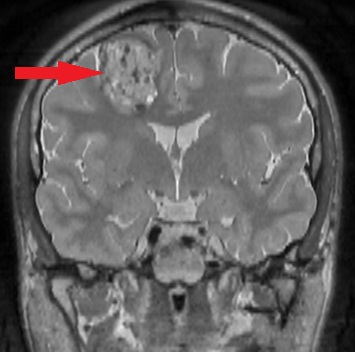

- Zmiany zapalne (np. stwardnienie rozsiane, ostre rozsiane zapalenie mózgu i rdzenia)